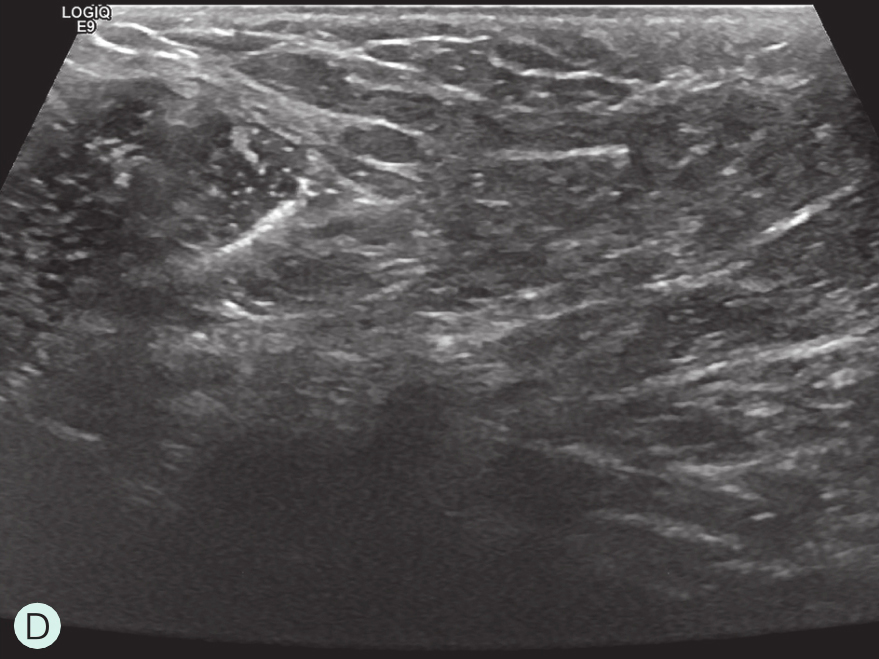

图2-2-1 确定造影病灶

A.病灶二维图像;B、C.病灶CDFI图像;D.同侧腋窝淋巴结情况;E.病灶弹性成像图像

造影前应用传统灰阶超声全面扫查患侧乳腺及腋窝,重点扫查既往检查可疑病灶所在象限,结合既往检查确定超声造影靶目标及造影切面。评估病灶所在部位乳腺腺体致密性,二维及彩色多普勒(CDFI)超声常规检测肿块的大小、形态、边界、内部回声、血流及与周边组织的关系,充分利用现有超声新技术(如弹性成像)全面评估病灶。当病灶位置表浅、位于乳头后方或与探头耦合不佳时,可应用超声垫。